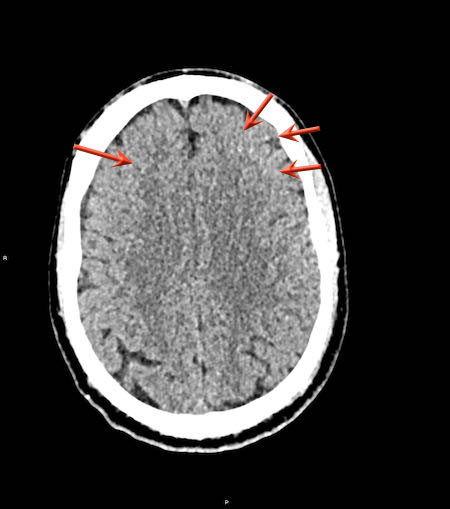

Tụ máu dưới màng cứng đồng tỷ trọng

Khi tụ máu dưới màng cứng tiến triển theo thời gian, tỷ trọng của khối tụ máu sẽ giảm dần và có thể tương đương với tỷ trọng của nhu mô não, khiến việc phát hiện tổn thương trở nên khó khăn.

Đây là trường hợp tụ máu dưới màng cứng đồng tỷ trọng rất khó phát hiện (các mũi tên).

Lưu ý rằng ở mức cắt cao hơn có tụ máu dưới màng cứng hai bên.